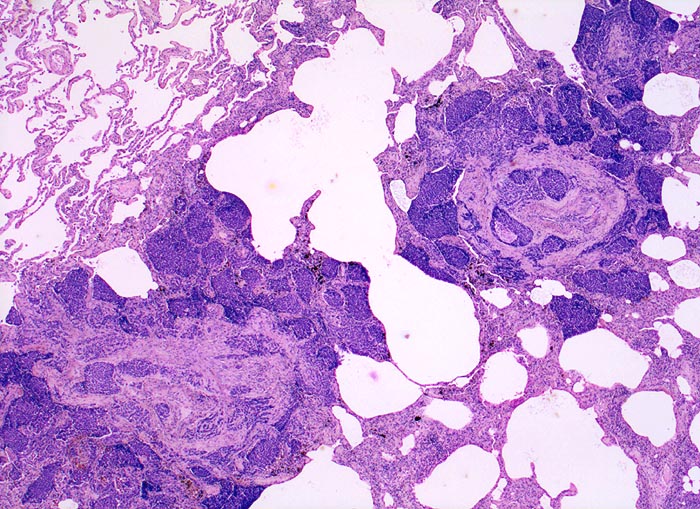

Das metastatische Wachstumsmuster von primären Bronchuskarzinomen und extrapulmonalen Tumoren innerhalb der Lunge ist variabel. Hämatogene Metastasen imponieren makroskopisch als multiple scharf begrenzte rundliche Knoten in allen Lappen meist in peripherer Lage. Der metastatische Befall von Lymphknoten kann durch direkte Tumorinfiltration durch den Primärtumor erfolgen (=per continuitatem) oder über die Lymphgefässe. Bei einer ausgeprägten lymphogenen Tumorausbreitung erscheinen subpleurale mit Tumor gefüllte Lymphgefässe makroskopisch als prominente weisse Streifen. Mikroskopisch lassen sich Tumorinfiltrate in peribronchialen und perivaskulären Lymphgefässen nachweisen (=Lymphangiosis carcinomatosa). Hepatozelluläre Karzinome metastasieren typischerweise in Form von Tumorembolien (> 1279) hämatogen in die Lunge.

• In den sternförmigen Ausläufern finden sich erweiterte Endothelausgekleidete Lymphgefässe in der Nachbarschaft von Blutgefässen.

• Die erweiterten Lymphgefässe enthalten solide Tumorzellaggregate.

• Vermehrte Alveolarmakrophagen in den peritumoralen Alveolen mit phagozytiertem Anthrakose- und Hämosiderinpigment (Rauchermakrophagen).

• Peritumorales Lungenemphysem (Traktionsemphysem).